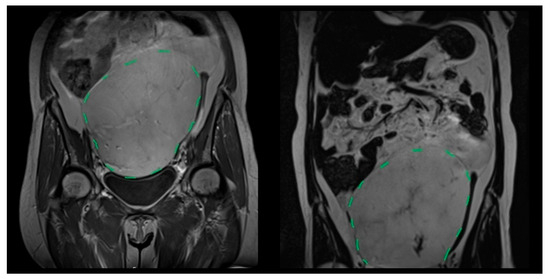

| Patient 1 | 55 | F | Jejunal | Well-differentiated | 20 × 15 × 12 | No | No | Alive | 76.4 |

| Patient 3 | 57 | M | Small bowel mesentery | Dedifferentiated | 19 × 15 × 13 | CT | Yes | Deceased | 158.0 |

| Patient 4 | 69 | F | Left colon | Dedifferentiated | 32 × 29 × 22 | No | Yes | Deceased | 0.4 |

| Patient 6 | 74 | M | Small bowel mesentery | Myxoid Liposarcoma | 28 × 19 × 13 | CT | Yes | Deceased | 45.4 |

| Patient 7 | 43 | F | Left colon | Myxoid Liposarcoma | 12 × 11 × 2 | RT-CT | Yes | Alive | 117.2 |

| Patient 8 | 42 | M | Jejunoileal and Colonic Mesentery | Myxoid Liposarcoma | 16 × 11 × 3 | No | No | Deceased | 1.4 |

| Patient 9 | 66 | M | Right Upper-Lower Quadrant | Well-differentiated | 26 × 21 × 28 (FNA biopsy) | No | - * | Deceased (metastatic disease) | - |

| Patient 10 | 40 | M | Left Lower Quadrant | Myxoid Liposarcoma | 17 × 14 × 11.5 | No | No | Alive | 71.8 |

| Patient 11 | 22 | F | Right Colon | Myxoid Liposarcoma | 23 × 18.5 × 15 | No | - | Alive | 35.7 |

| Patient 12 | 71 | M | Jejunoileal and Colonic Mesentery | Myxoid Liposarcoma | 19 × 19 × 14 | CT | - | Deceased | 14.8 |

| Patient 13 | 56 | M | From Pelvis to Right Hepatic Lobemesentery | Dedifferentiated | 35 × 20 × 10 | No | - | Alive | 35.8 |